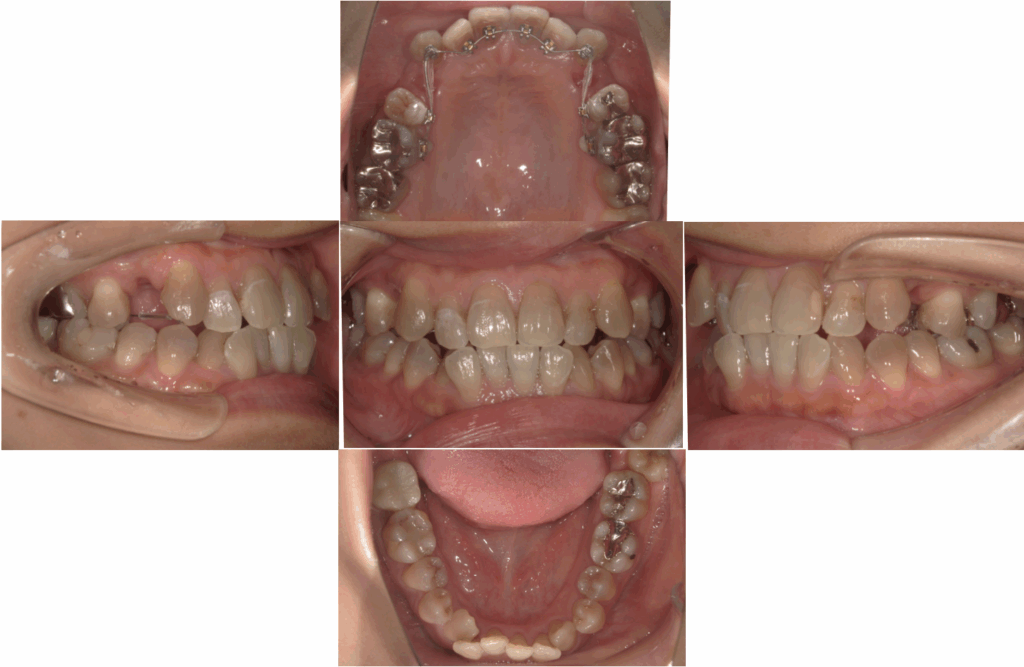

拝見すると、上の犬歯がやや外側に出ており、前歯部に**叢生(ガタガタ)**が見られました。

また、上下の真ん中(正中線)にも少しズレがありました。

3Dスキャンデータから歯並びを詳しく分析すると、上・下ともに前歯のガタつき(叢生)が明確に認められました。

特に上顎の犬歯がやや外側に位置し、下顎前歯は重なりが強い状態です。

また、上下の真ん中(正中線)にわずかなズレが見られ、咬み合わせも軽い前突傾向を示していました。